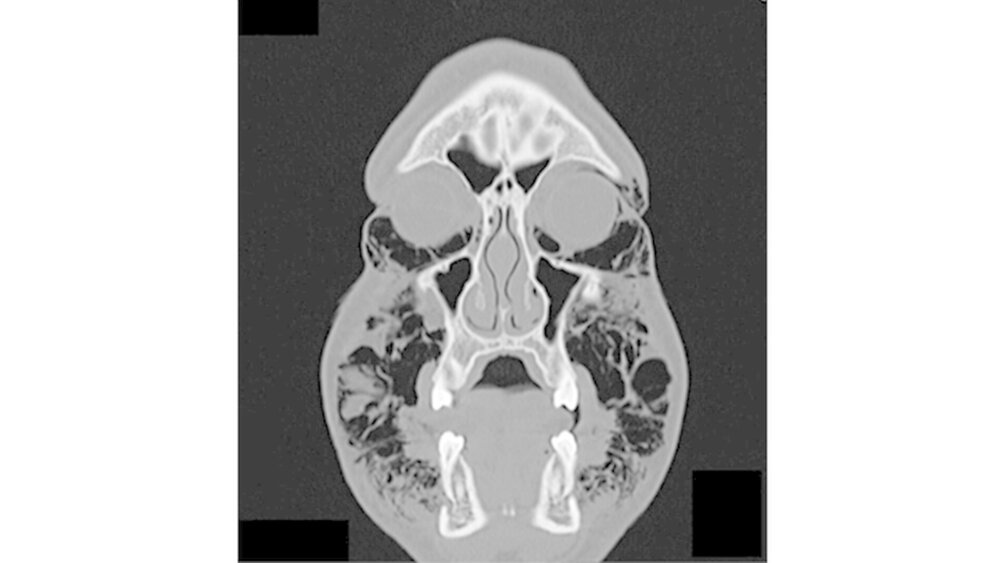

Permanent wiederholte er das Valsalva-Manöver, indem er Atemluft gegen seine verschlossenen Lippen presste. Bei der Aufnahme war der Patient hämodynamisch stabil. Die Funktionen von Nervus facialis sowie Nervus trigeminius waren normal. Auch die Entzündungswerte befanden sich im normalen Bereich. Klinisch war eine umfangreiche Schwellung im gesamten Gesichtsbereich sichtbar. Zudem hatte der Patient Schwierigkeiten, die Augen zu öffnen (Abbildungen 1 und 2).

Bei der Palpation war eine offensichtliche Schwellung der Periorbitalregion, der Wangen sowie der Supraklavikulargruben tastbar. Der enorale Befund zeigte eine nicht vollständig geschlossene Extraktionsalveole. Eine Entzündung war jedoch nicht zu erkennen. Mundboden und Rachenbereich waren von der Luftansammlung nicht betroffen. Der Patient konnte schlucken, doch das Atmen fiel im schwer.